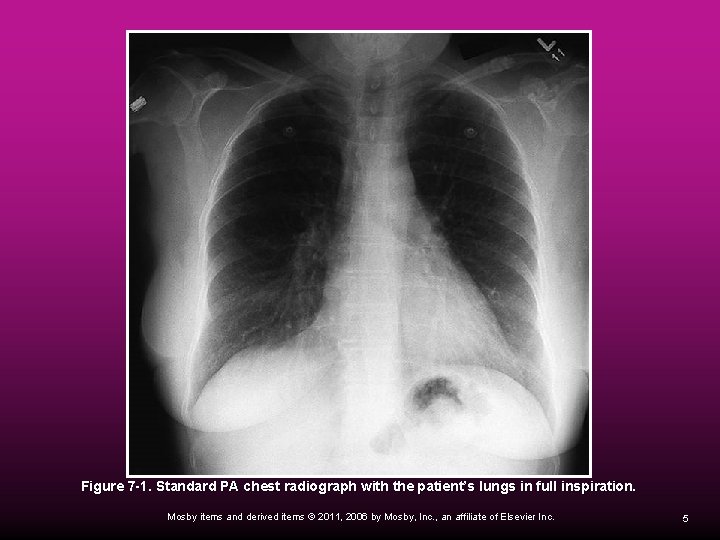

Posteroanterior Radiograph The standard PA chest radiograph is obtained by having the patient stand (or sit) in the upright position. The anterior aspect of the patient’s chest is pressed against a film cassette holder. Mosby items and derived items © 2011, 2006 by Mosby, Inc. , an affiliate of Elsevier Inc. 4

Figure 7 -1. Standard PA chest radiograph with the patient’s lungs in full inspiration. Mosby items and derived items © 2011, 2006 by Mosby, Inc. , an affiliate of Elsevier Inc. 5